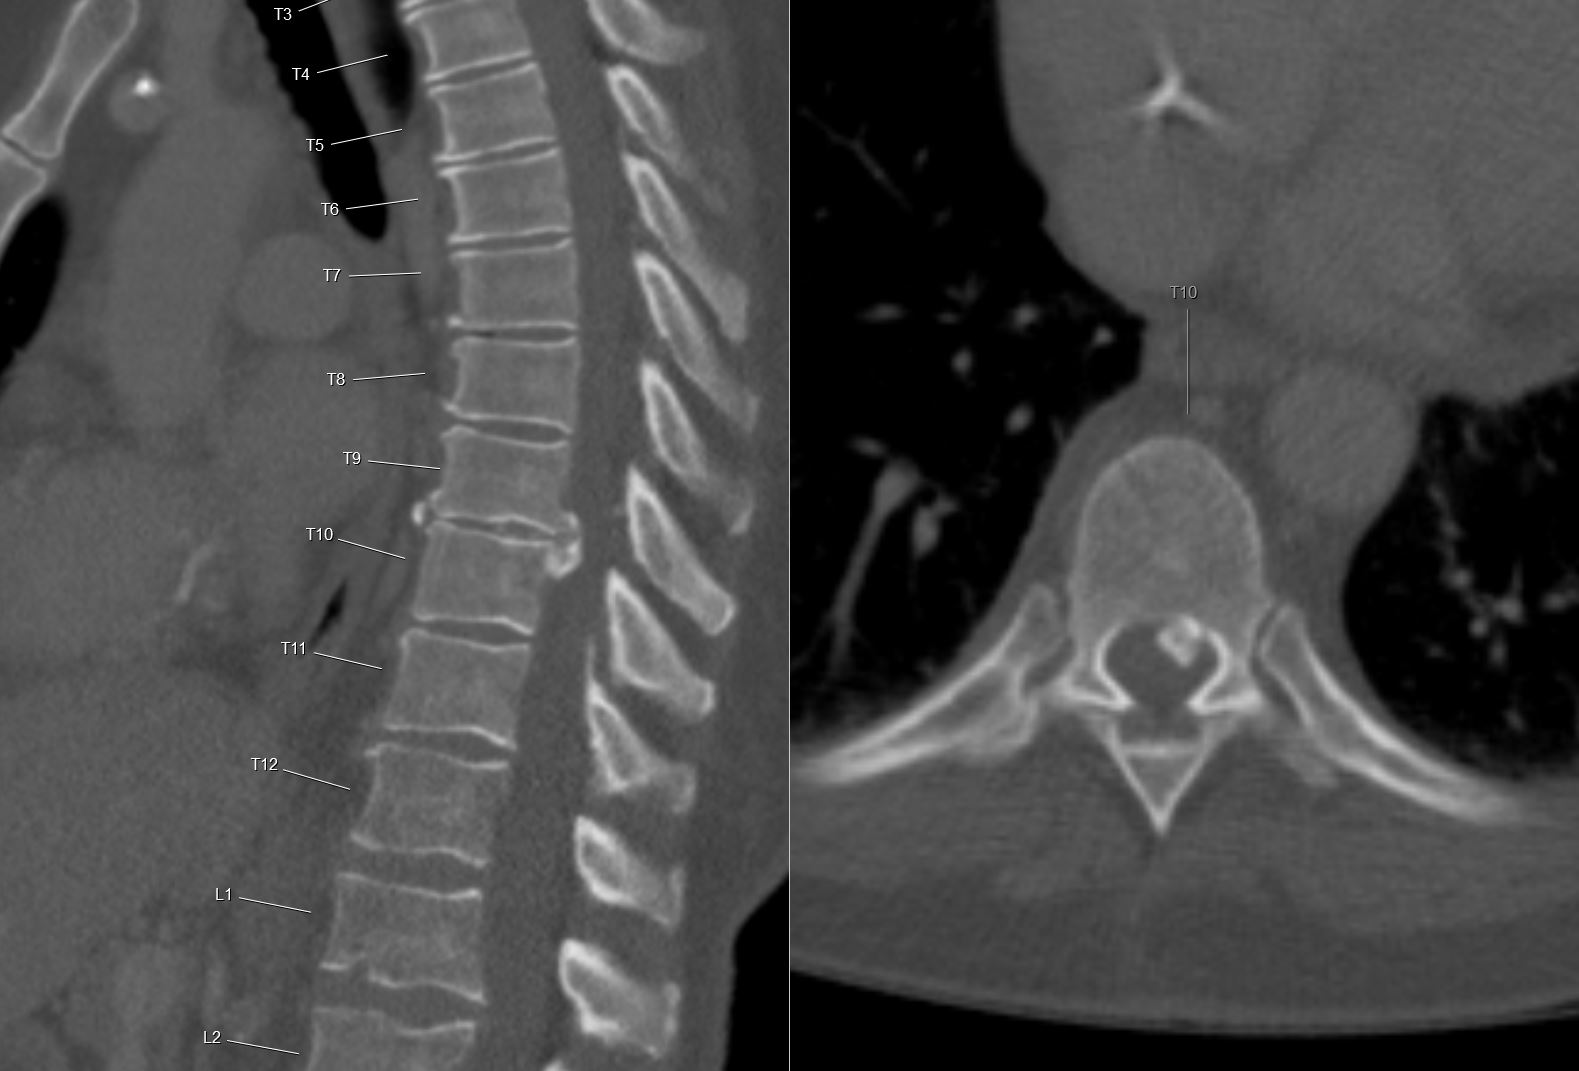

Figure 1 from A calcified thoracic intervertebral disk with herniation Intervertebral Disc Calcification Radiology This may occur in isolation or in conjunction. To determine the prevalence, distribution, and location of intervertebral disk calcification (idc) in the. Intervertebral disc (ivd) calcification is associated with ivd degeneration and can lead to pain. It is frequently seen as a consequence of disc aging and progressive degeneration but exhibits unique molecular and. Ivd calcification may affect disc. It. Intervertebral Disc Calcification Radiology.

Calcified Thoracic Disc Herniation Intervertebral Disc Calcification Radiology It may be observed in paediatric 5 as well as adult populations. Ivd calcification may affect disc. It is frequently seen as a consequence of disc aging and progressive degeneration but exhibits unique molecular and. Intervertebral disc (ivd) calcification is associated with ivd degeneration and can lead to pain. Annulus fibrosus calcification is a form of intervertebral disc calcification where. Intervertebral Disc Calcification Radiology.